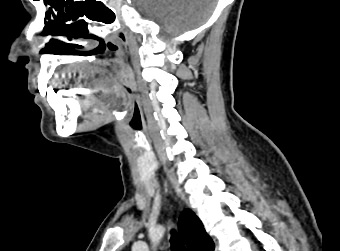

Мультиспиральная компьютерная томография – это высокоинформативный лучевой метод диагностики различной патологии мягких тканей шеи, включая воспалительные заболевания, травматические повреждения и опухолевые процессы. КТ позволяет оценить состояние щитовидной железы, паращитовидных желез, гортани, верхней части пищевода, магистральных сосудов шеи, шейных лимфоузлов и окружающих мягких тканей.

Метод КТ основан на применении рентгеновского излучения. Однако в отличие от обычного рентгена, при котором снимки производятся в одной плоскости, при КТ излучатель рентгеновских лучей постоянно двигается вокруг объекта исследования, проводя сканирование в различных плоскостях, а затем трансформируя полученные данные в цифровые трехмерные изображения. Это дает возможность визуализировать органы и ткани в мельчайших подробностях, а с помощью объемных 3D-реконструкций наглядно оценить пространственное расположение органов и патологических образований.

Рентгеновские лучи лучше всего поглощаются плотными структурами, такими как костная ткань. Поэтому кости хорошо видны на снимках КТ. Это делает компьютерную томографию незаменимой при необходимости обследования, в частности, костного скелета гортани. Однако для улучшения визуализации мягких тканей требуется введение специального контрастного препарата, поэтому КТ мягких тканей шеи проводится с контрастным усилением.

Для контрастирования используется йодсодержащее контрастное вещество, которое в составе рентгеноконтрастного препарата вводится в вену пациенту непосредственно во время исследования. Благодаря способности контраста поглощать рентгеновские лучи на снимках КТ хорошо контрастируются кровеносные сосуды и опухолевые образования, имеющие, как правило, развитую сосудистую сеть. Методика внутривенного болюсного контрастирования помогает обнаружить воспалительные изменения, отличить доброкачественные опухоли от злокачественных, выявить поражение лимфатических узлов и степень прорастания опухоли в магистральные сосуды и окружающие ткани.